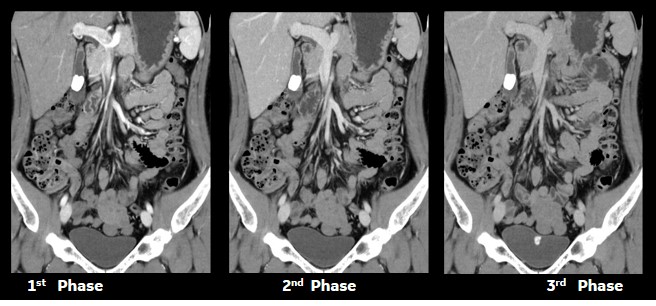

マルチフェイズ造影検査のDelay時間設定

16列では1相ごとの撮影時間を次相のDelay時間を引いて造影プロトコルを個々の検査毎に修正していたが、Maximaでは注入開始からのDelay設定時間で2相目以上の撮影が行えるようになりました。また、1相毎に異なるシリーズ番号を割り振って、個々にWW・WL幅を設定して画像データを設定された画像サーバー、ワークステーションへの自動転送が可能になりました。

腹部造影検査のMPR

16列では撮影範囲・線量の問題で1.25㎜厚で再構成しMPRを作成していたが、Maximaでは0.625㎜厚で再構成しコロナル画像を作成している。 最新の逐次近似によるノイズ除去機能ASiR-Vを再構成に加えることにより、薄スライスMPRの高画質での画像化が可能になり、MRI画像との対比が容易になりました。